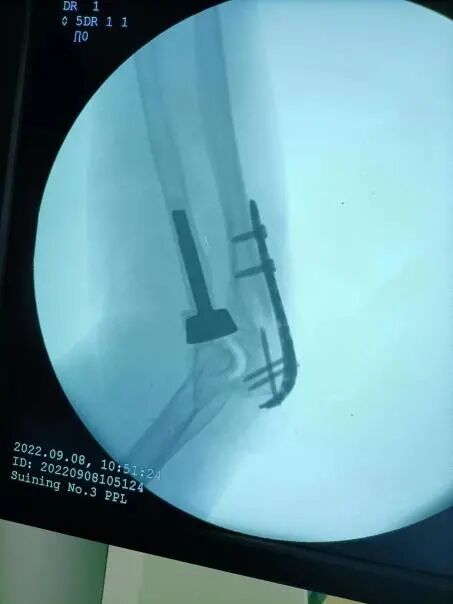

面对如此复杂的损伤,经骨伤科专家团队讨论,迅速为唐女士制定了“三管齐下”治疗计划。经过与患者和家属充分沟通并征得同意后,罗斌为患者实施了左尺骨骨折切开复位钢板内固定、尺骨冠状突修复、左人工桡骨头置换术,“快,准、稳”地为患者成功完成手术。

(术中C臂透视)